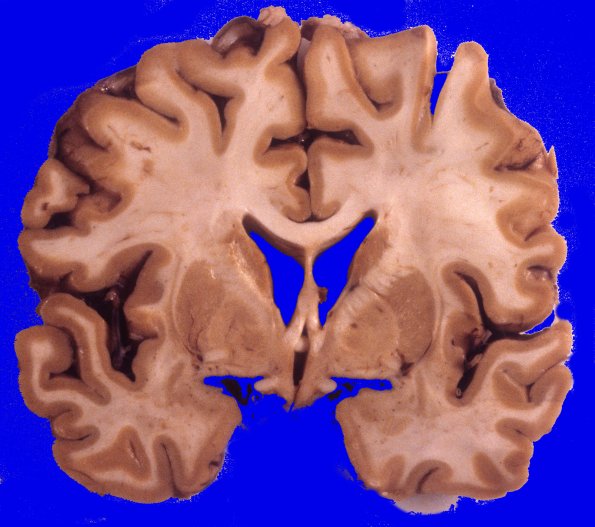

Neuronal Ceroid Lipofuscinosis (NCL)

3A3 Neuronal Ceroid Lipofuscinosis (Case 3) A11